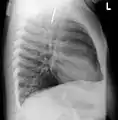

القنوات التنفسية

إن دخول جسم غريب إلى القنوات التنفسية يمكن أن يتسبب بشرقة.[1]